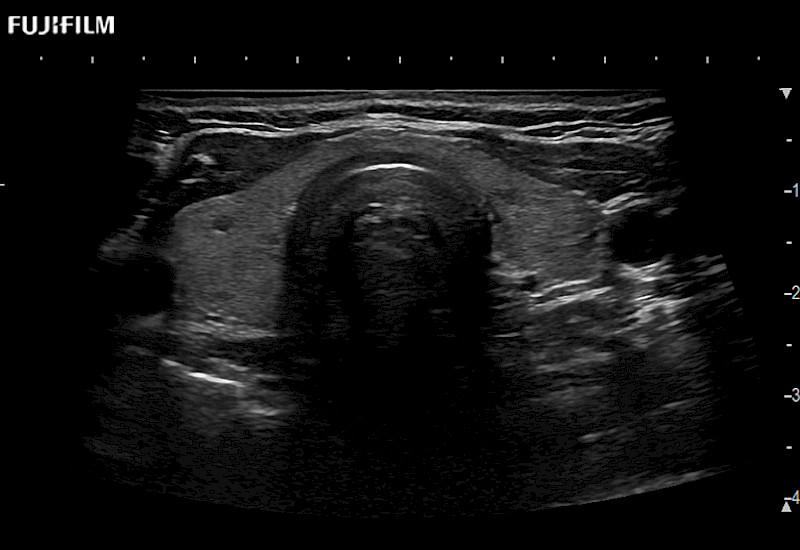

Extraordinary high-resolution digital imaging

- Exceptional near and far-field resolution

- Instant feedback on tumor margin delineation

- Valuable information to guide tumor resections

- Exceptional near and far-field resolution

- Instant feedback on tumor margin delineation